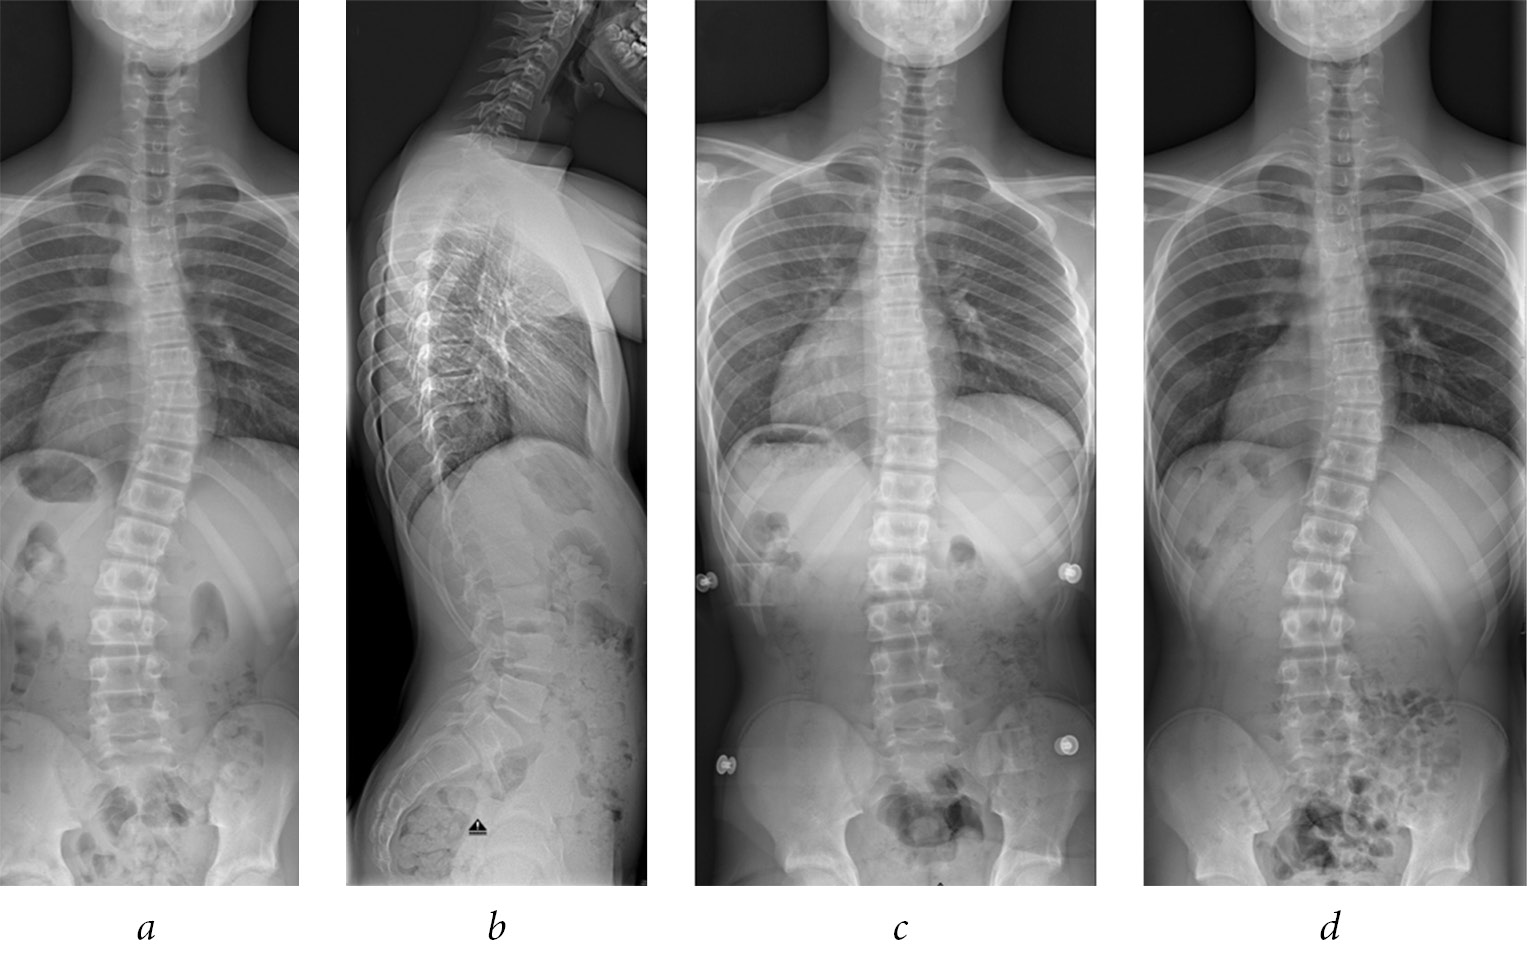

After approval of the institutional ethical review committee of the University Medical Center, a cohort of 52 AIS patients from a single medical university center, which were treated conservatively with a Chêneau brace therapy were followed from the beginning of treatment until the end of growth and several months (average nine months) after brace therapy. According to Richards et al. [15] SRS (scoliosis research society) paper on brace studies, inclusion criteria at the beginning of brace treatment were the diagnosis of AIS, minimum age of ten years, Risser sign 0 to 2 (<50% ossification of the iliac apophysis on radiographs), scoliotic curve angle (Cobb degree) between 25° and 40°, less than one year after the menarche and no prior treatment. Patients who satisfied these criteria and who were treated with a Chêneau brace until the end of skeletal growth (Risser sign 5), were included into this study. Additionally, 14 patients with a scoliotic curve angle of 17°–24° were included as brace therapy is suggested at 20° of scoliosis in Germany and a measurement error of 5° should be considered using the Cobb method. Clinical data such as curve patterns and body mass index were documented. Standardized radiological standing images in the AP (anterior-posterior) and lateral projections at the first visit were performed and analyzed. In order to reduce radiation exposure, follow-up radiographs were performed as an AP standing film only (Fig. 1).

Fig. 1. A 12-year old boy with scoliosis (a) and a normal sagittal profile (b). Scoliosis could be well corrected by a Chêneau brace (c). At six months follow-up after the end of brace treatment, spinal deformity was similar to the initial values (d)

All patients were prescribed a Chêneau brace, which were manufactured at different companies throughout the country. After completion of the brace, a period of adjustment was recommended with increasing wear duration. If necessary, an adaptation of the orthosis was performed by the manufacturing company. An outpatient visit was scheduled three to five months after the initial visit to check on the brace and to perform AP radiographs in the brace to proof deformity correction. All adolescents and their parents were instructed to wear the brace for 23 hours/day [14] and only to take it off during sports and showers. Physiotherapy was prescribed with a given preference to the Schroth method to de-rotate, stabilize and elongate the spine in a three-dimensional plane [16]. Objective data on real brace time wearing and physiotherapy effors were not collected. Therefore, the reported data represent a typical everyday situation in a large pediatric spine clinic.